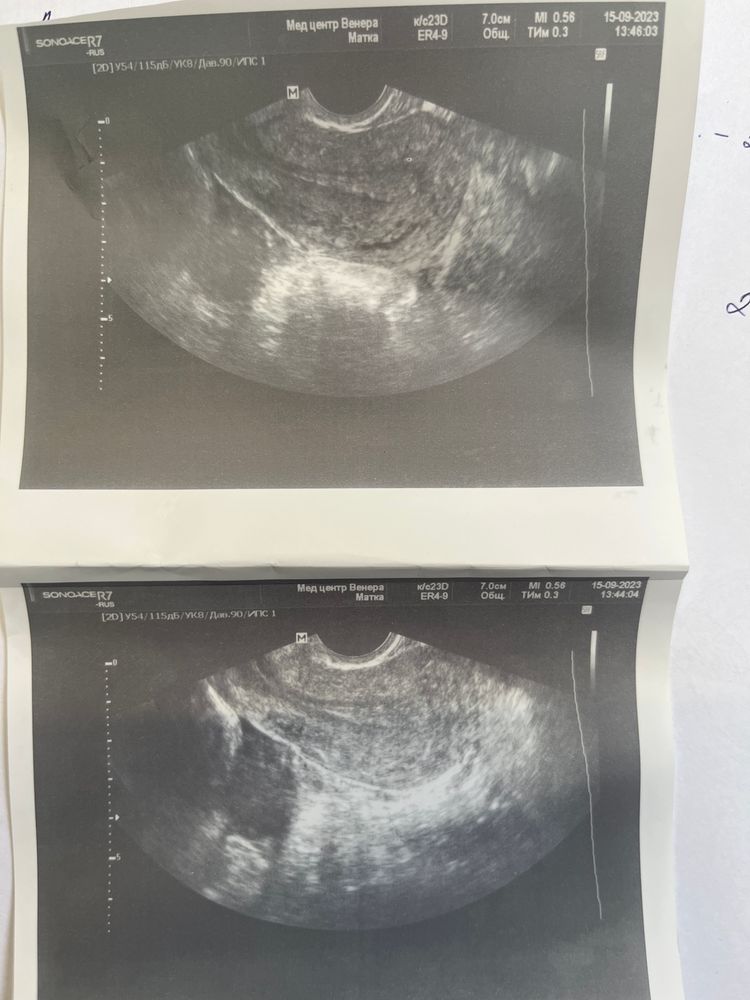

Mira, Изображение Изображение

Сделала узи для подтверждения 26 день цикла, я так понимаю овуляции не было , про желтое тело ничего не сказали, значит пролет?